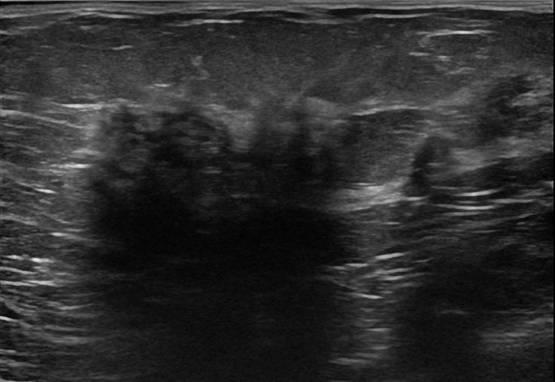

Ung thư vú

» Thông tin: Nữ giới – 58 tuổi.

» Lâm sàng: Khối tuyến vú.